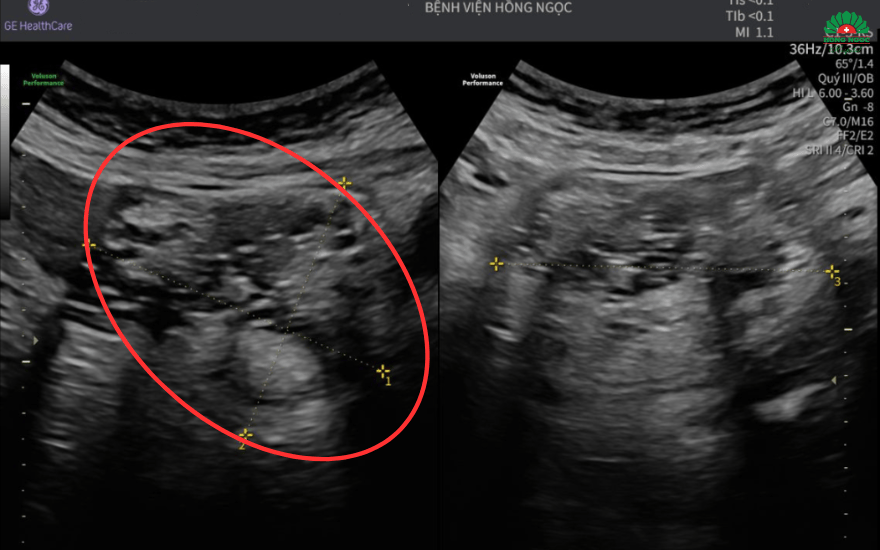

Tại đây, chị được chỉ định siêu âm và chụp MRI ổ bụng, kết quả cho thấy u buồng trứng kích thước hơn 7cm cùng hình ảnh mô đặc, mỡ, xương - gợi ý u quái trưởng thành. Để ngăn chặn biến chứng ảnh hưởng đến sức khỏe, các bác sĩ quyết định thực hiện phẫu thuật nội soi loại bỏ khối u cùng hai phần phụ.

Khối u buồng trứng kích thước hơn 7cm chèn ép các tạng xung quanh - Ảnh BVCC

“Mặc dù khối u có kích thước không quá lớn nhưng đã kéo cả tử cung và buồng trứng lên quá rốn, chèn vào bàng quang. Vì vậy, ê-kíp phẫu thuật phải hết sức tỉ mỉ để loại bỏ được toàn bộ khối u cùng các tổ chức bất thường, đồng thời không làm ảnh hưởng đến các cơ quan lân cận”, ThS.BS Nguyễn Thị Thùy - Phó Trưởng khoa Sản Phụ khoa, Bệnh viện Đa khoa Hồng Ngọc Phúc Trường Minh - bác sĩ trực tiếp điều trị cho bệnh nhân T. chia sẻ.